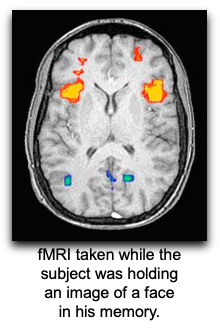

Where is the central executive processor in the brain? [1]

prefrontal cortex